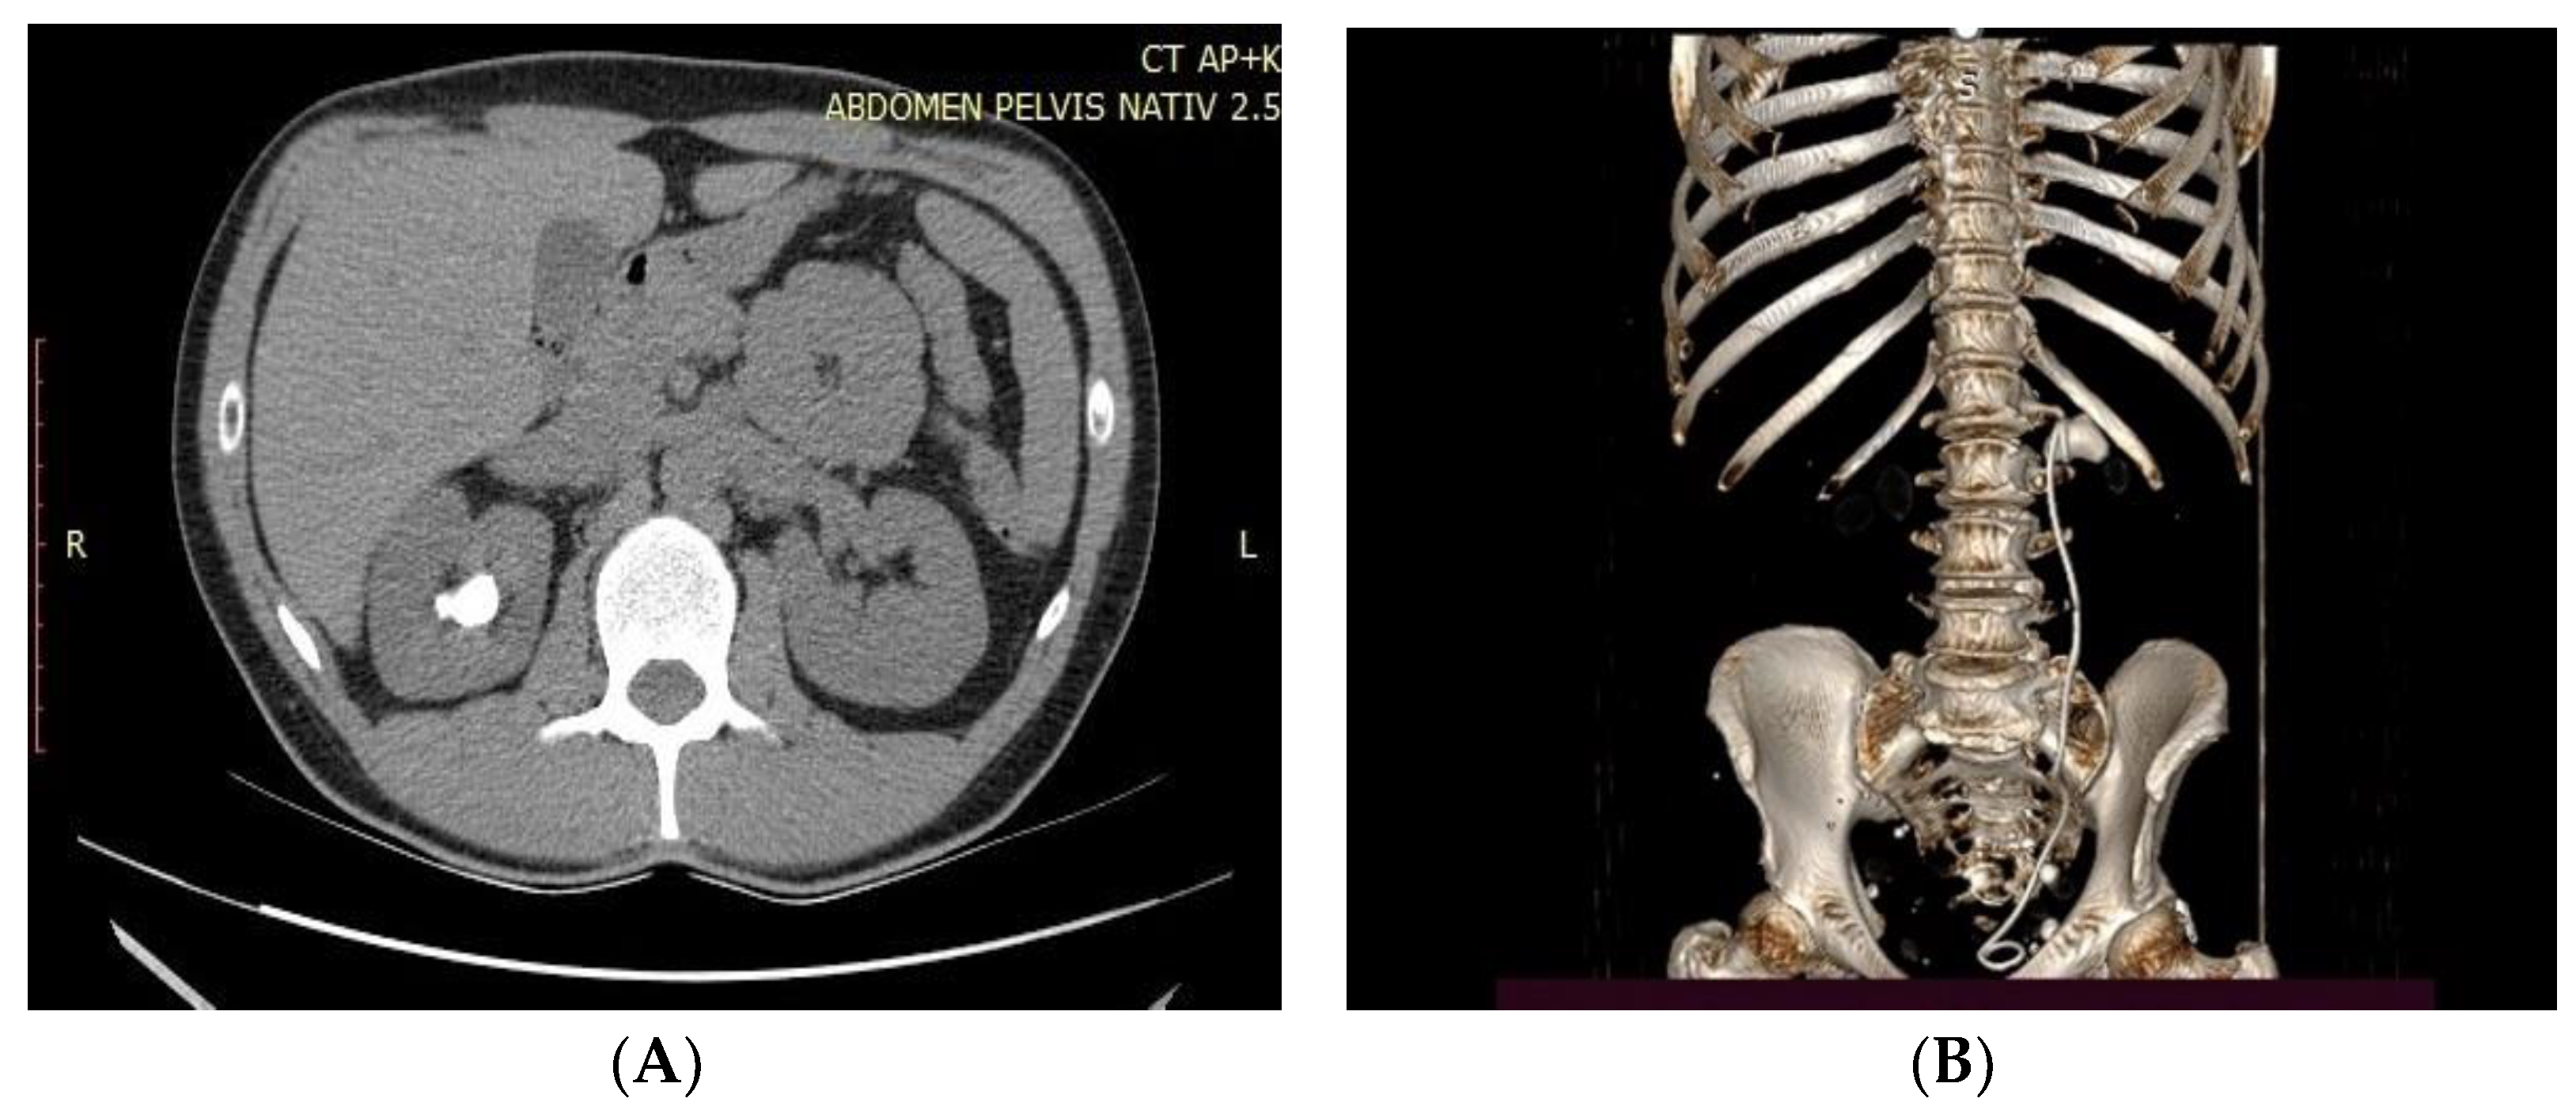

We retrospectively analyzed 250 consecutive patients with large renal solitary stones (stone burden between 2 and 4 cm) from 1 January 2019 to 31 December 2020. The patients were divided into two groups: group 1 (125 patients), in which the patients were treated by a retrograde flexible ureteroscopic approach, and group 2 (125 patients), in which patients were treated by percutaneous nephrolithotomy. Stone characteristics and anatomical data were observed based on the computed tomography (CT) and/or KUBradiography imaging archive. For larger stones, more than one session of flexible ureteroscopy was necessary. The preoperative CT images calculated the stone surface area based on the largest volume (length × width  =  mm2). The follow-up evaluation was undertaken one month after the operation using plain film of KUB(Kidney-ureter-Bladder) for opaque stones, ultrasonography for non-opaque stones, or non-contrast CT of the whole abdomen (Figure 1A,B).

Figure 1. (A,B). CT scan image and reconstruction of large pelvic stone.